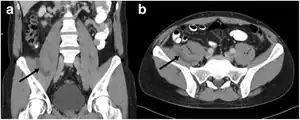

| CT scan: right-sided retroperitoneal hibernoma | |

In general, imaging studies show a well-defined, heterogeneous mass, usually showing a mass which is hypointense to subcutaneous fat on magnetic resonance T1-weight images. Serpentine, thin, low signal bands (septations or vessels) are often seen throughout the tumor.